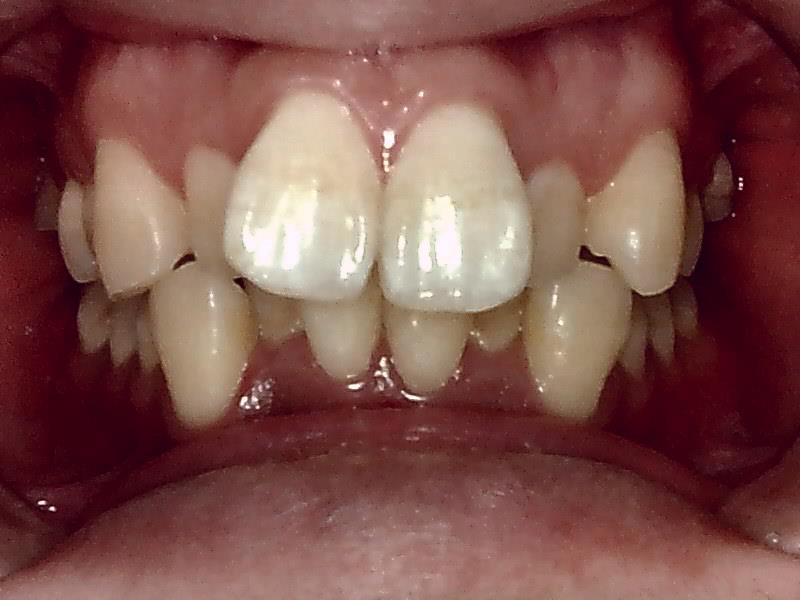

術前口腔内写真 正面観

○前歯の前突した歯を治したい

○八の字型の歯並びを改善したい

○笑った時の歯のアーチを綺麗にしたい